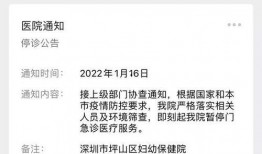

梅州最新爆料消息今天疫情,揭秘病毒传播轨迹与防控措施”

你知道吗?最近梅州又有了新的疫情动态,这可是个大新闻呢!今天,我们就来聊聊这个话题,看看梅州疫情的最新情况。梅州疫情最新进展首先...

2025-12-04 17 -